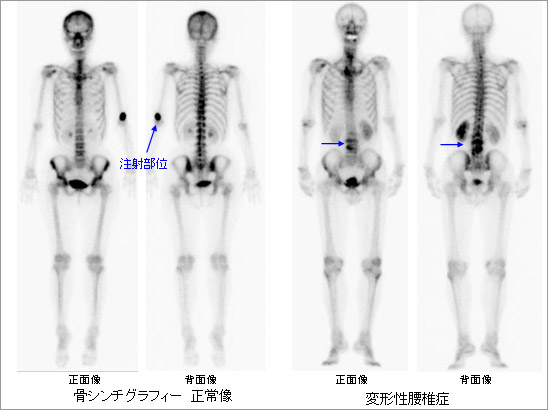

全身骨シンチグラフィ 乳癌 肺癌 前立腺癌等の骨転移病巣の検出

前立腺がんの検査 骨シンチグラフィー 前立腺がんの治療と名医

主な核医学検査 骨 骨シンチグラフィ 核医学検査のご案内 医療関係者

骨シンチグラフィーとは 佐賀大学病院放射線科アンオフィシャル

全身骨シンチグラフィ 乳癌 肺癌 前立腺癌等の骨転移病巣の検出

骨シンチグラフィによる骨転移の診断 Bone Scan Ct Mri画像診断